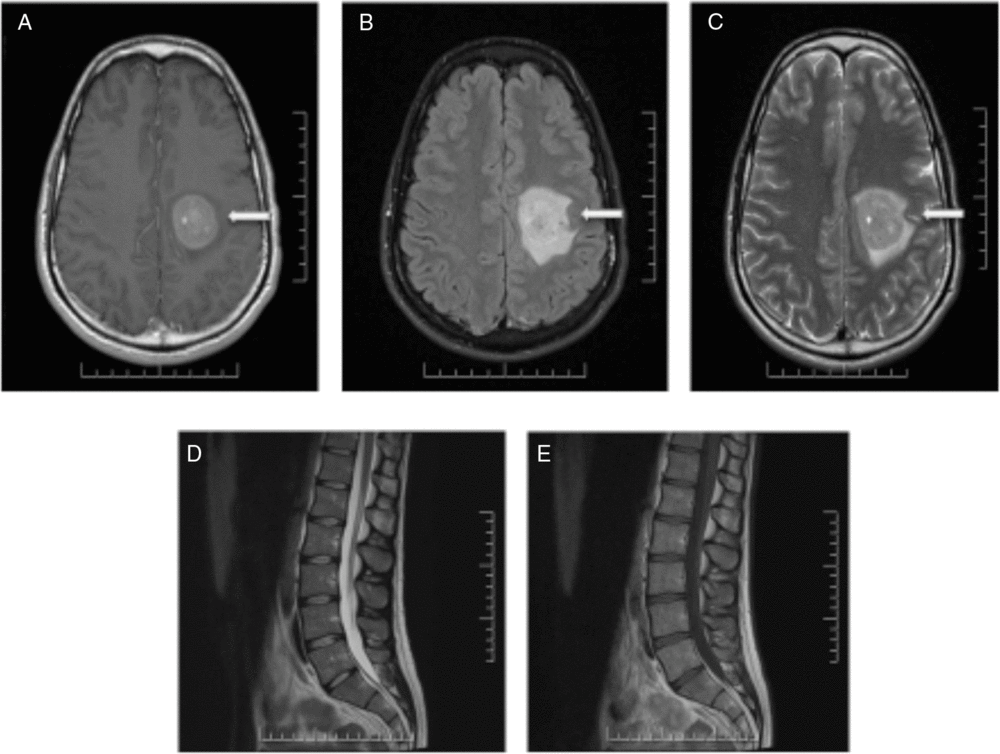

Nine months after the initial presentation, new progressive right-sided weakness developed. MRI of the brain and spine demonstrated a new large enhancing lesion in the left centrum semiovale with surrounding halo of restricted diffusion (Figure 2). No cauda equina enhancement was seen, and previously seen enhancement in the right internal auditory canal and left Meckel’s cave resolved. Four expert neuroradiologists debated the diagnosis of Balo’s concentric sclerosis versus central nervous system (CNS) lymphoma. Three additional high-volume lumbar punctures 5 days apart were performed. Cytology of all CSF samples was negative for malignancy, and flow cytometry was negative for monoclonality. Computed tomography imaging of the thorax, abdomen and pelvis was performed and was normal.

Figure 2: MRI of the brain and spine demonstrating a large enhancing lesion in the left centrum semiovale (A–C). No cauda equina enhancement was seen and previously seen enhancement in the right internal auditory canal and left Meckel’s cave resolved (D,E).